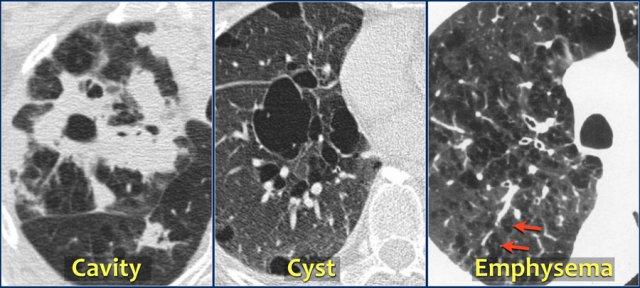

Các nhà X quang sử dụng nhiều thuật ngữ để mô tả các vùng giảm tỷ trọng hoặc vùng sáng trong phổi, như nang, hang, phế nang khí (pneumatocele), khí phế thũng, bóng khí (bulla), tổ ong, bóng khí nhỏ (bleb), v.v.

Một cách tiếp cận thực tế hơn là mô tả các vùng giảm tỷ trọng trong phổi như sau:

- Hang – vùng sáng có thành dày

- Nang – vùng sáng có thành mỏng

- Khí phế thũng – vùng sáng không có thành rõ ràng

Hang thường hình thành bên trong một khối hoặc vùng đông đặc do hoại tử.

Trong chẩn đoán phân biệt, có sự chồng lấp giữa hang và nang.

Hang có thể lành và trở thành nang phổi, và nang phổi có thể bị nhiễm trùng, biến thành hang có thành dày.

Đôi khi các bóng khí trong khí phế thũng có thành rõ với độ dày dưới 1 mm.

Để phân biệt chúng với nang, cần quan sát nhu mô phổi xung quanh.

Nang xuất hiện mà không kèm theo khí phế thũng.

Nang thường chứa khí, nhưng đôi khi chứa dịch hoặc thành phần đặc.

Thuật ngữ này chủ yếu được dùng để mô tả các khoang khí thành mỏng giãn rộng ở bệnh nhân mắc bệnh u cơ trơn bạch huyết (lymphangioleiomyomatosis) hoặc bệnh mô bào Langerhans.

Nang tổ ong có thành dày hơn được gặp ở bệnh nhân xơ hóa phổi giai đoạn cuối (11).